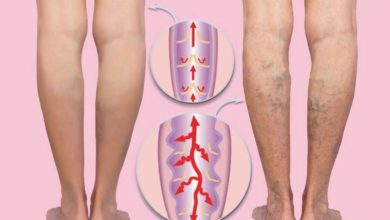

علاج دوالي الساقين بالأعشاب في المنزل | هل فعال؟

تتعدى نسبة إصابة الأشخاص البالغين بدوالي الساقين ٢٥٪ وتحدث الدوالي في أي من أوردة الجسم لكنها أكثر شيوعًا في أوردة…